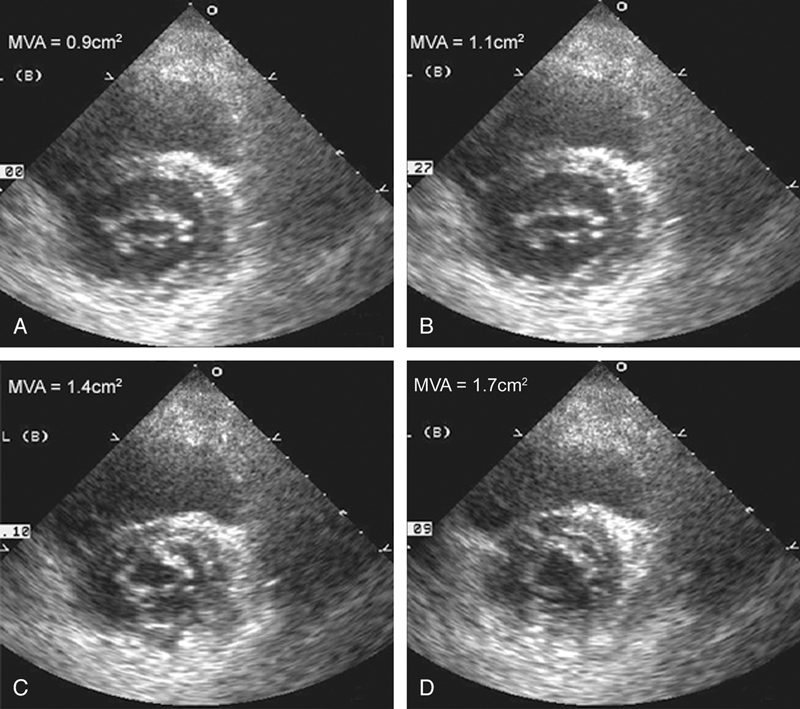

فحوصات تشخيصية لبعض امراض القلب والشرايين التاجية